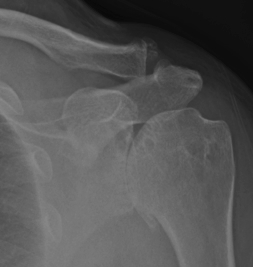

Here’s an example:

The picture on the left highlights a portion of the shoulder blade called the acromion where bone spurs commonly arise. Bone spurs in this area can be a normal part of the aging process and MAY NOT be the source of your pain.

Far more people have bone spurs in their shoulder on the acromion (left picture) than inside the joint (right picture).